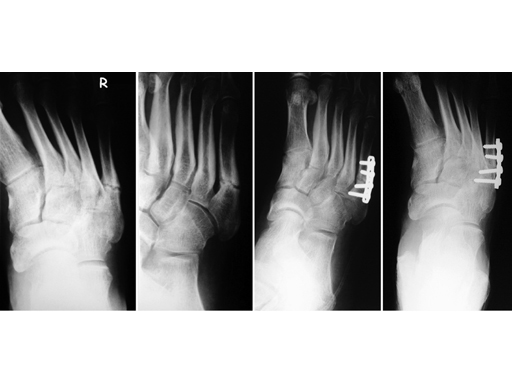

Jones fracture with pseudarthrosis in a 58-year-old man

Fixation with a 4-hole LC-DCP 2.7 whereby dynamic compression was achieved using 3.5 mm screws.